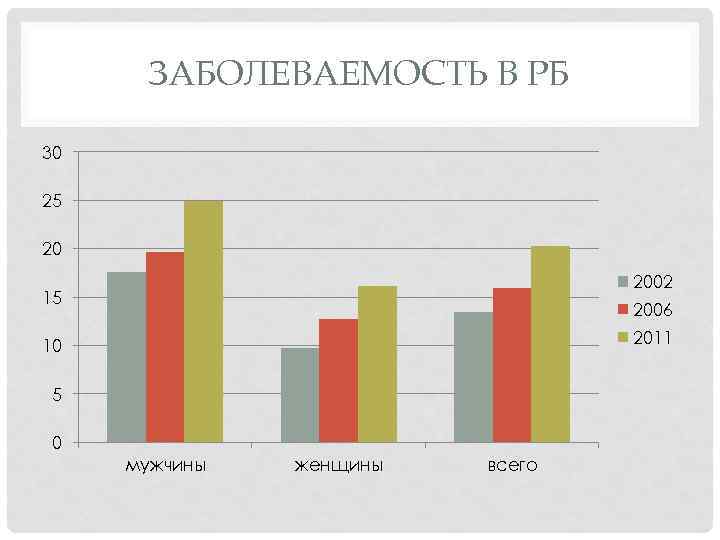

ЗАБОЛЕВАЕМОСТЬ В РБ 30 25 20 2002 15 2006 2011 10 5 0 мужчины женщины всего